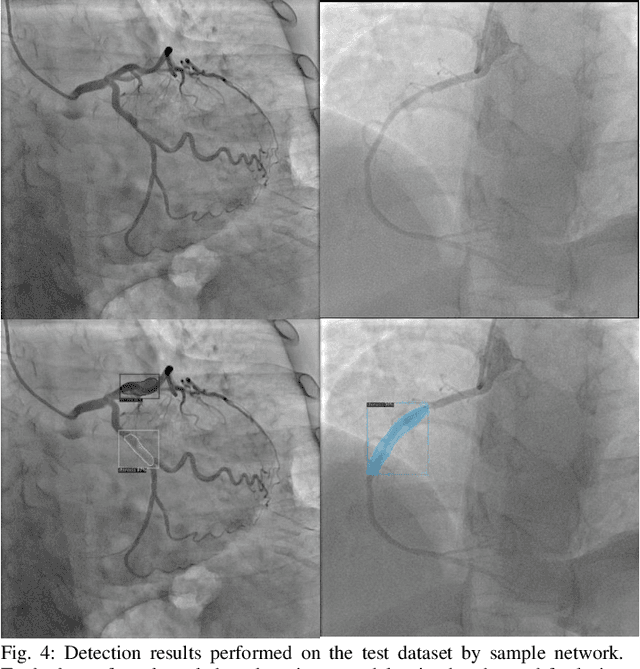

Abstract:Coronary Heart Disease (CHD) is a leading cause of death in the modern world. The development of modern analytical tools for diagnostics and treatment of CHD is receiving substantial attention from the scientific community. Deep learning-based algorithms, such as segmentation networks and detectors, play an important role in assisting medical professionals by providing timely analysis of a patient's angiograms. This paper focuses on X-Ray Coronary Angiography (XCA), which is considered to be a "gold standard" in the diagnosis and treatment of CHD. First, we describe publicly available datasets of XCA images. Then, classical and modern techniques of image preprocessing are reviewed. In addition, common frame selection techniques are discussed, which are an important factor of input quality and thus model performance. In the following two chapters we discuss modern vessel segmentation and stenosis detection networks and, finally, open problems and current limitations of the current state-of-the-art.